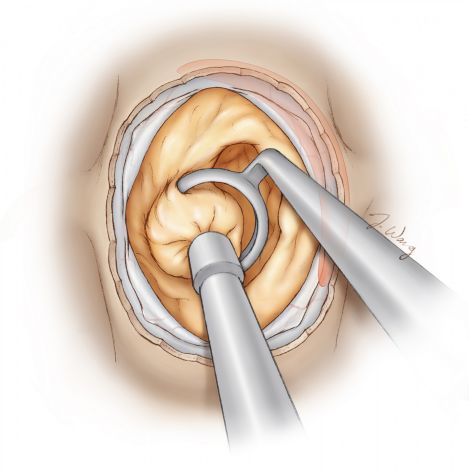

图10. 肿瘤前上部分一般较难切除,因其有损伤毗邻结构特别是鞍膈的风险。这是术后肿瘤残留的另一常见原因;残余的肿瘤将继续导致视神经压迫症状。成角内镜可在这一区域提供良好视野。为暴露肿瘤,可轻轻牵开垂体。为避免肿瘤残余,需磨除足够的骨窗。(引自Tew, van Loveren, Keller*,有改动).

图11. 鞍结节上方(鞍前隐窝)的肿瘤与鞍膈粘连(插入图),若强行盲切,可能导致鞍膈破裂,引起脑脊液漏。辨别鞍膈并在切除肿瘤时保持其完整非常重要。若不慎造成鞍膈破裂,笔者一般使用事先准备的取自患者腹部的自体脂肪准确封堵裂口,避免用力填塞整个蝶鞍,此操作可能导致鞍上占位效应,导致视力障碍。(引自Tew, van Loveren, Keller*).